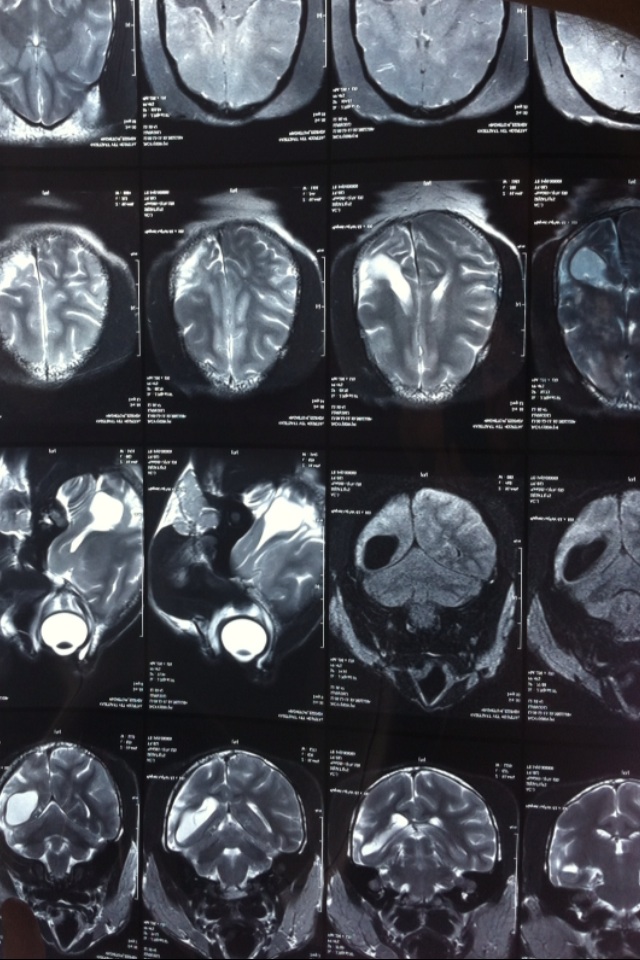

MRI (Magnetic Resonance Imaging) for primates at WFFT

As in human medicine, advanced imaging techniques like MRI scans are required to diagnose disorders of the brain and nervous system in animals. So, when the medical team at the WFFT wildlife hospital encountered 2 new primate rescues with brain and spinal cord injuries, an appointment was made at Chulalongkorn University Veterinary hospital in Bangkok for MRI scans to investigate.

‘Jacky’ a white cheeked gibbon with chronic brain damage and ‘Pixie’ a baby long tailed macaque with a spinal injury underwent brief general anaesthesia for the scans which revealed promising treatment options for both. After years of daily, debilitating seizures ‘Jacky’ has been diagnosed with hydrocephalus (water on the brain) and ‘Pixie’ who was paralysed from the waist down has a spinal fracture but will walk and climb again with the right care. WFFT vets are working alongside specialist neurologists to devise the treatment plans and both are already responding.

Jacky’s brain damage makes him a uniquely gentle gibbon. He lacks the usual strength, agility and aggression of his species and can be handled closely by his vet and carers since they have gained his trust. MRI brain scans at Kasetsart Veterinary University hospital diagnosed hydrocephalus (water on the brain) which means the condition may be treatable. Trials of human anti-epileptic drugs have given promising results in stabalising jacky’s seizures and we are working closely with specialist neurologists to give Jacky a more normal life